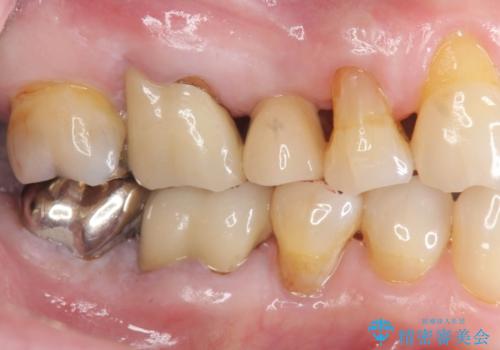

失った奥歯のインプラント治療

- 失ったままで放置していたインプラント治療を希望され来院されました。

抜歯後から十分に時間が経過しており、すぐにインプラントの埋入を計画できる状態です。

- 44万円(インプラント・チタンカスタムアバットメント・ジルコニアクラウン・仮歯)費用は治療当時の料金となります

「失った1本の歯の機能回復を行うだけでもずいぶん咬めるようになった。」、と咬合機能の回復を実感していただくことができました。